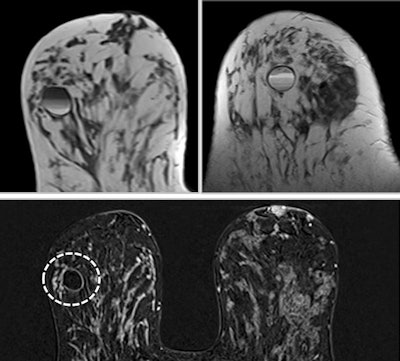

Comet sign: A lesion with enhancement characteristics that typically exhibits a "tail" that extends into the parenchyma, frequently oriented toward the nipple, resembling the tail of a comet. When a "comet tail" emerges from an enhanced lesion, it serves as a robust indicator of early ductal carcinoma in situ, particularly when it points toward the nipple or aligns with the ductal system. Less probable scenarios, which can be readily discerned from the patient's medical history, include previous biopsies or surgeries in the preceding months. All images courtesy of Dr. Karina Pesce, PhD, and presented at RSNA 2023.